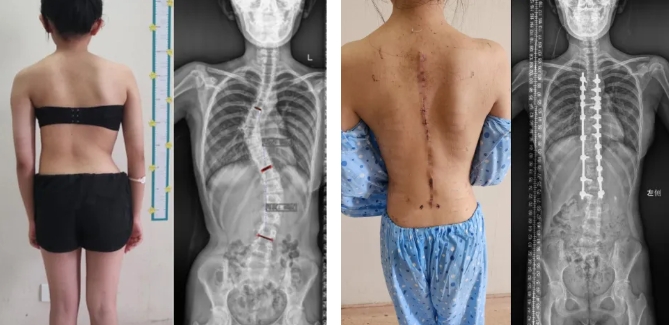

案例二:

13岁的中学生小林,9岁发现特发性脊柱侧弯,初始侧弯最大角度33°,经过诊治后,小林开始佩戴支具外固定治疗,但仍未能阻止病情的进展。小林10岁时复查,发现侧弯度数仍有增大,并出现腰背部频发疼痛等症状,且侧弯度数在持续性加重。小林在家人的陪同下来到集团就诊,由邱勇院士亲自主刀进行了脊柱侧弯的矫形手术,小林术后感觉腰背痛已经明显减轻,畸形已恢复,目前随诊1年余,病情稳定,且无并发症发生。